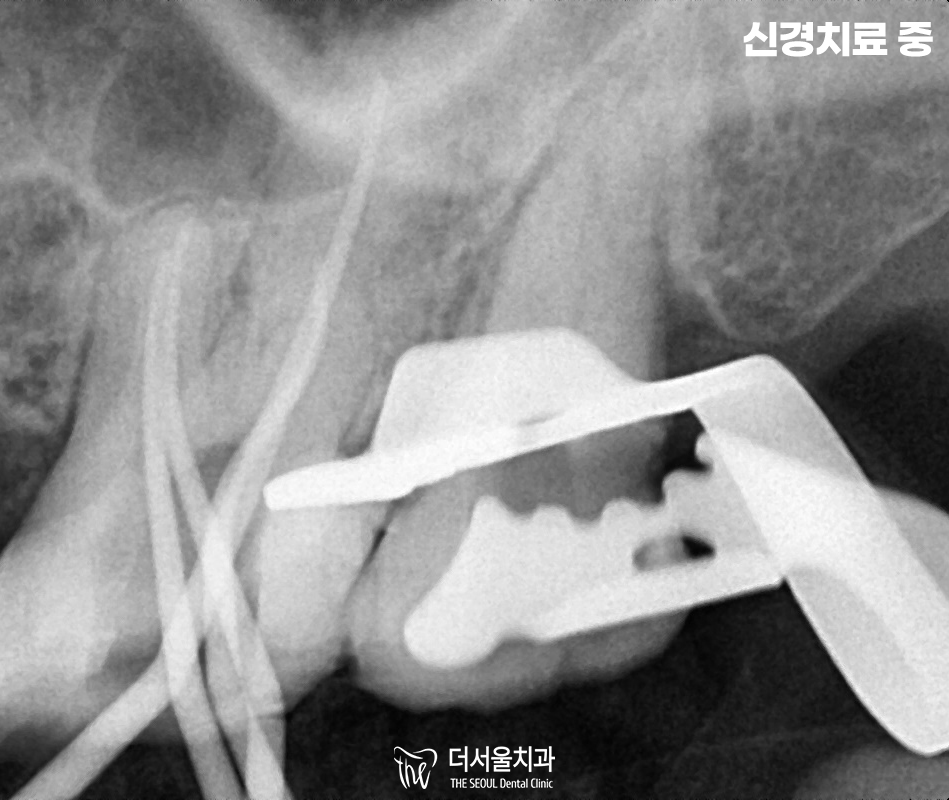

『26, 27 어금니 신경치료 시작』

감염된 조직을 모두 제거 후,

깨끗하게 소독을 여러번 진행하여

재발하는 일이 없도록 해드렸습니다.

이후, GP cone이라는 것을 넣어

빈 근관을 충전해줍니다.